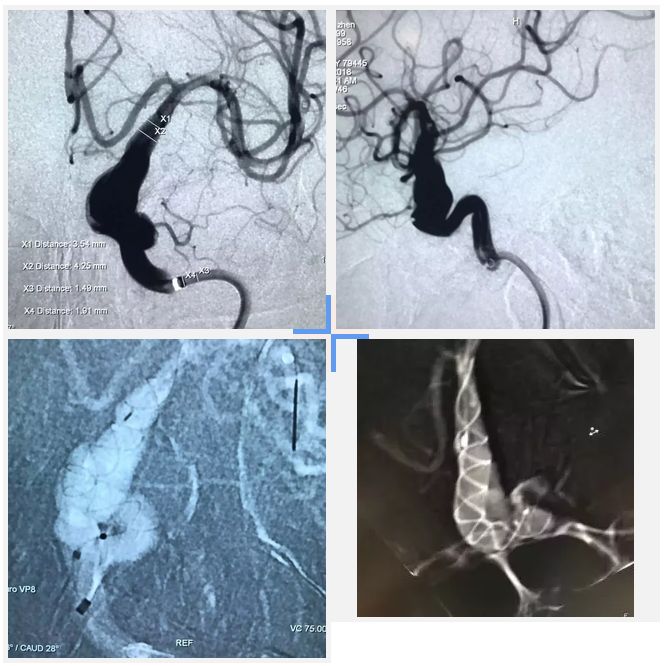

病例二

患者,女,60岁,长节段梭型动脉瘤,植入Tubridge®4.0mm*45mm,从造影到结束射线照射时间不到10分钟,效果满意,期待长期随访结果。